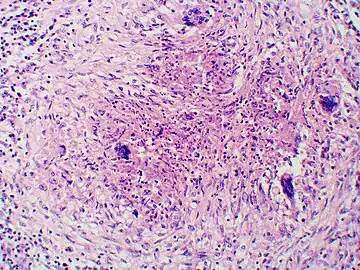

Granuloma with early suppuration. Fungal organisms difficult to recognize at this low magnification.

Granuloma with early suppuration. Fungal organisms difficult to recognize at this low magnification. Large yeast-like fungi seen within giant cells at arrows.